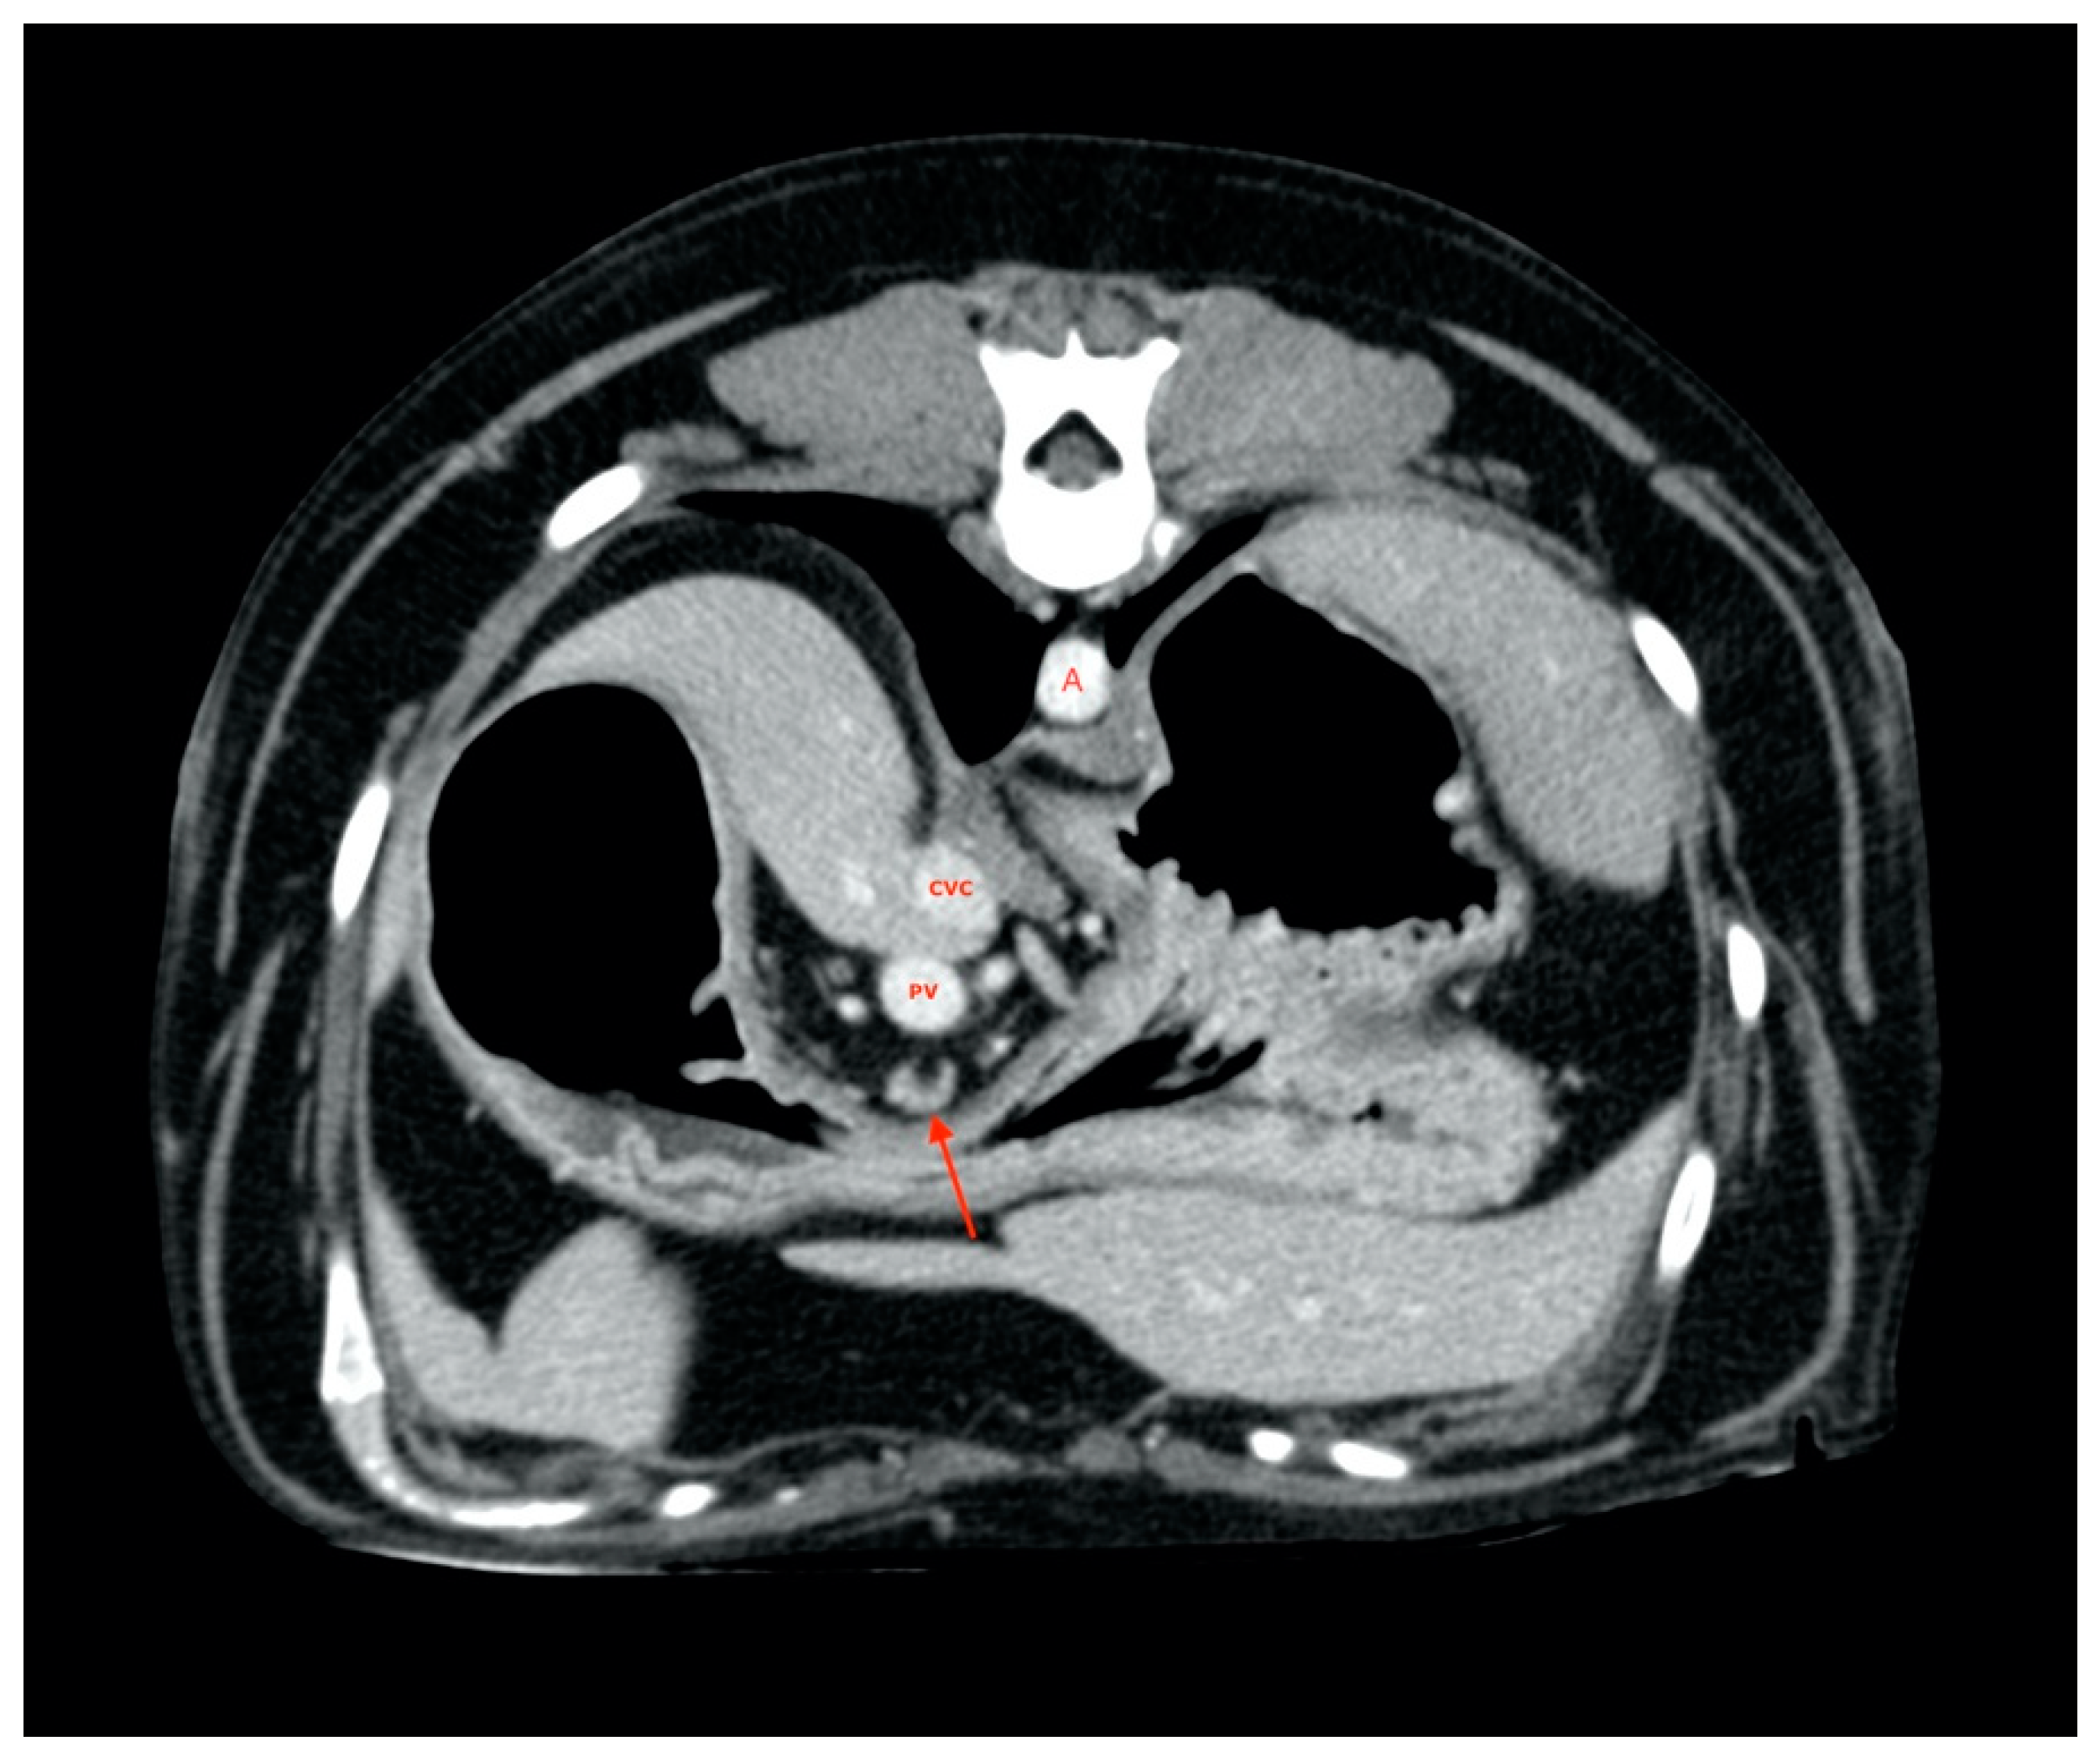

2.5. Measurements